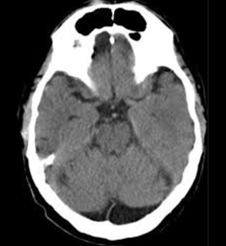

Sistema ventricular

El primero de todos es la asimetría ventricular, caso en el que observamos a un ventrículo de mayor tamaño respecto al contralateral sin que esto signifique hidrocefalia. Esto lo podemos corroborar al identificar las astas temporales de similar tamaño.

Fig. 1.

El segundo error habitual puede producirse ante la presenta de una coartación ventricular. Esto consiste en un contacto de las paredes ependimarias sin valor patológico suele ser confudnido con lesiones con efecto de masa.

Fig. 2.